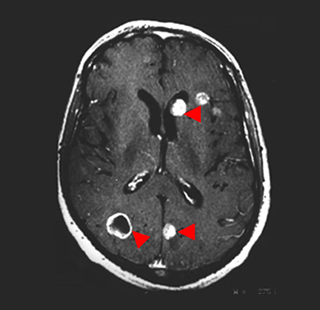

뇌 MRI

- 폐암은 뇌로 전이될 가능성이 높기 때문에, 뇌 MRI는 폐암 환자에서 뇌 전이를 확인하는 데 사용됩니다. 조기에 뇌 전이를 발견하면 치료 계획을 수정하여 환자의 예후를 개선할 수 있습니다.

폐암은 매우 치명적인 암이지만, 조기 발견과 적절한 치료로 생존율을 크게 높일 수 있습니다. 폐암 진단 후 시행되는 뇌 MRI, 뼈스캔, PET-CT 검사는 암의 확산 범위를 평가하고 적절한 치료를 계획하는 데 필수적입니다. 또한, EGFR, ALK 유전자 변이와 PD-L1 검사는 맞춤형 치료법을 선택하는 데 중요한 역할을 합니다. 비소세포암과 소세포암의 병기 구분 역시 치료 전략을 수립하는 데 중요한 기준이 됩니다. 이러한 정보를 바탕으로 환자와 의료진이 함께 최적의 치료 계획을 세우는 것이 중요합니다.